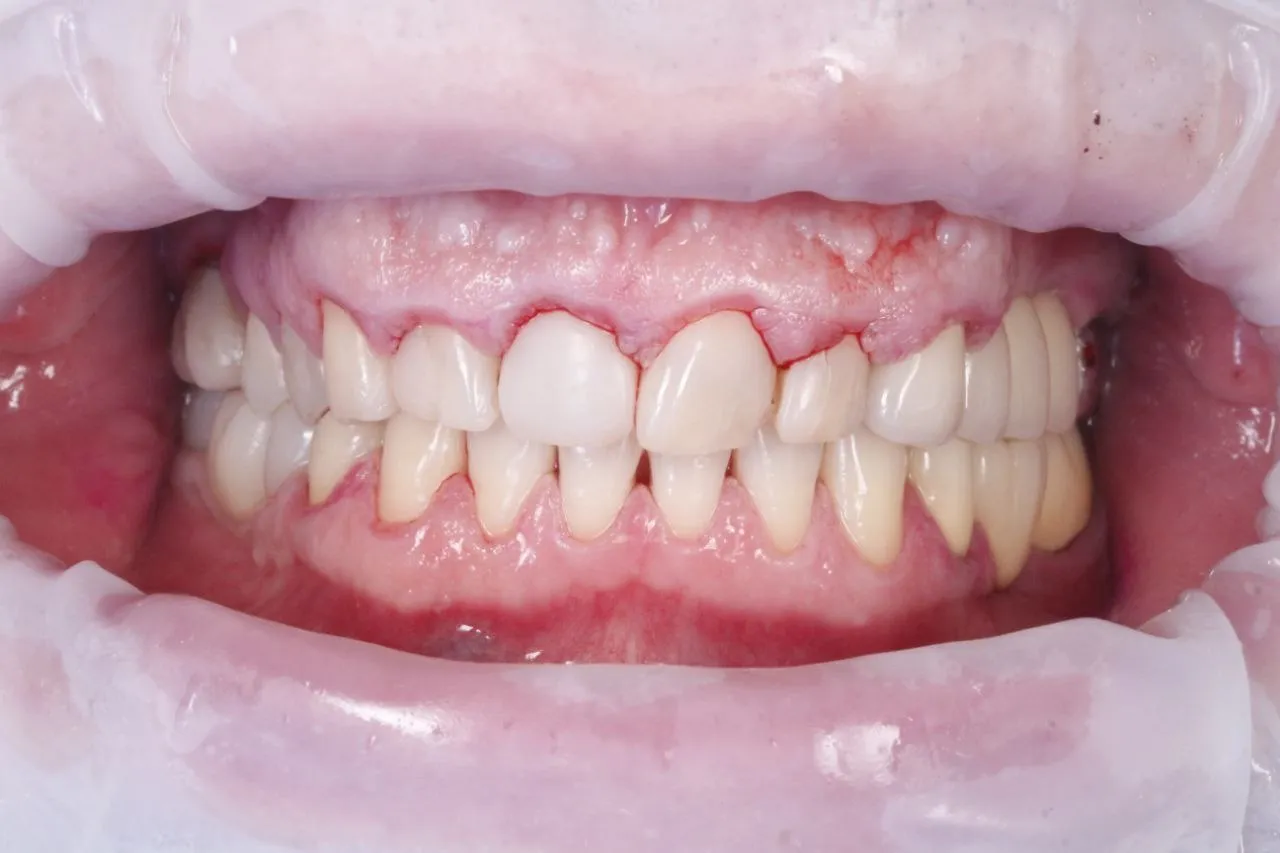

Лікування карієсу зубів 1.7.та 1.6.